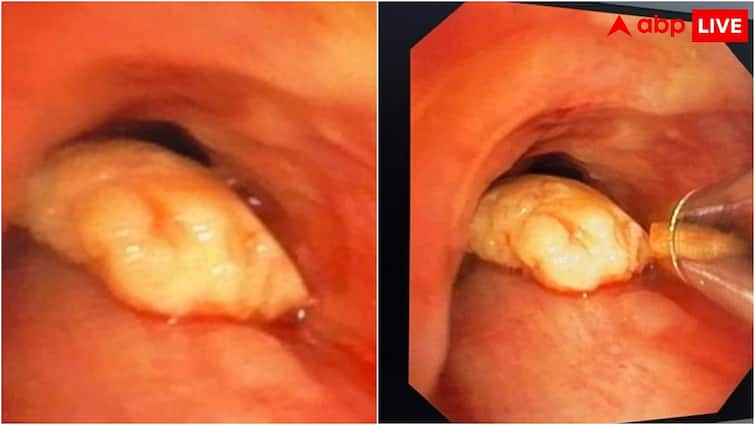

The woman had to cough and breathe for the past few days, after which the family took her to the local hospital. When the woman’s CT scan and X-ray was found, a piece of cashew was found stuck in her windpipe. An attempt was made to evacuate him with the help of endoscopy in the local hospital, but that effort was not successful. In such a situation, the woman was admitted to AIIMS Gorakhpur.

The team of Dr. Kanupriya and Dr. Raghav under the leadership of Dr. Subodh of Pulmonary Medicine Department of AIIMS carried out this complex bronchoscopy process. This process used state-of-the-art equipment such as video-broskope, cryo machine and Doria basket. This operation was performed in OT with extreme vigilance and technical accuracy. During this time, Dr. Winner Bajpai and Dr. Priyanka Dwivedi of the Department of Anesthesia provided support in the entire process. This joint functioning of both departments gave the woman a new life. After the operation, the condition of the woman is said to be stable and she is getting healthy normally. The operation and guidance of Major General Dr. Vibha Dutta, Executive Director of AIIMS Gorakhpur, was done to this operation. His inspiration and organizational efficiency encouraged the medical team to act accurately and dedicated.